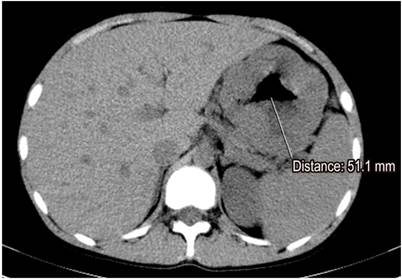

Paraclinical tests including a complete blood count, albumin, nitrogen and urine analysis were requested. The patient was found to have normocytic, normochromic, heterogeneous anemia. His hemoglobin level was 11.2 g/dL, his serum albumin level was 2.8 g/dL, and his creatinine level was 0.8 mg/dL (normal). The urine analysis did not find proteinuria. Given the clinical, paraclinical and endoscopic findings, computed tomography (CT) of the abdomen was performed. It found thickened gastric walls with diffuse, marked and symmetric gastric folds without evidence of nodular lesions. The maximum thickness was 53 mm (Figure 1). Findings from gastric endoscopic ultrasonography (EUS) were similar to those described of the upper digestive tract endoscopy, but thickening of the gastric wall dependent on the first and second echoic layers (mucosa and muscular mucosa, respectively) was found. Anechoic spaces were found in the second echoic layer respecting the third and fourth echoic layers (submucosa and muscularis propria, respectively) (Figure 2).

Endoscopically, the folds of the gastric mucosa are markedly thick especially in the fundus and the corpus rather than in the antrum. Gastric pH is high due to the loss of parietal cells, and there is copious production of thick mucus secondary to foveolar hyperplasia that occurs most commonly in the mucosa. This causes mucosal thickness to increase by one cm or more (in our clinical case it reached 5 cm). This is a necessary condition for diagnosis. 5